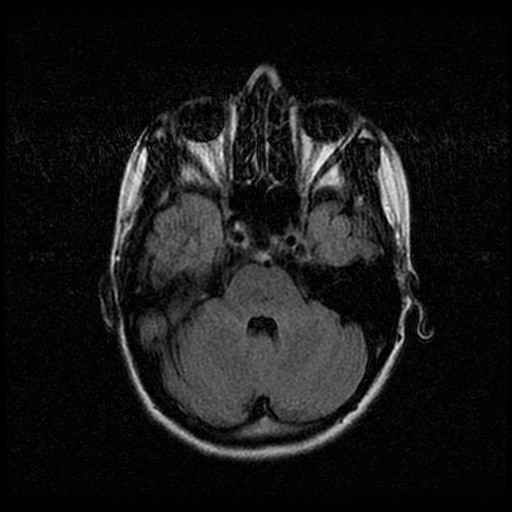

Schedel